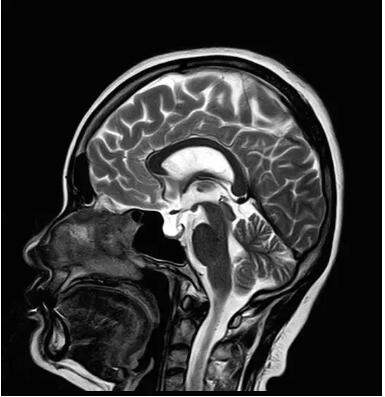

佳能磁共振推出了全新一代Vantage Elan1.5T磁共振,這款日本原裝進口的 1.5T磁共振,集當今磁共振創(chuàng)新科技成果于一身:

Pure 射頻影像鏈——圖像信噪比提升40%